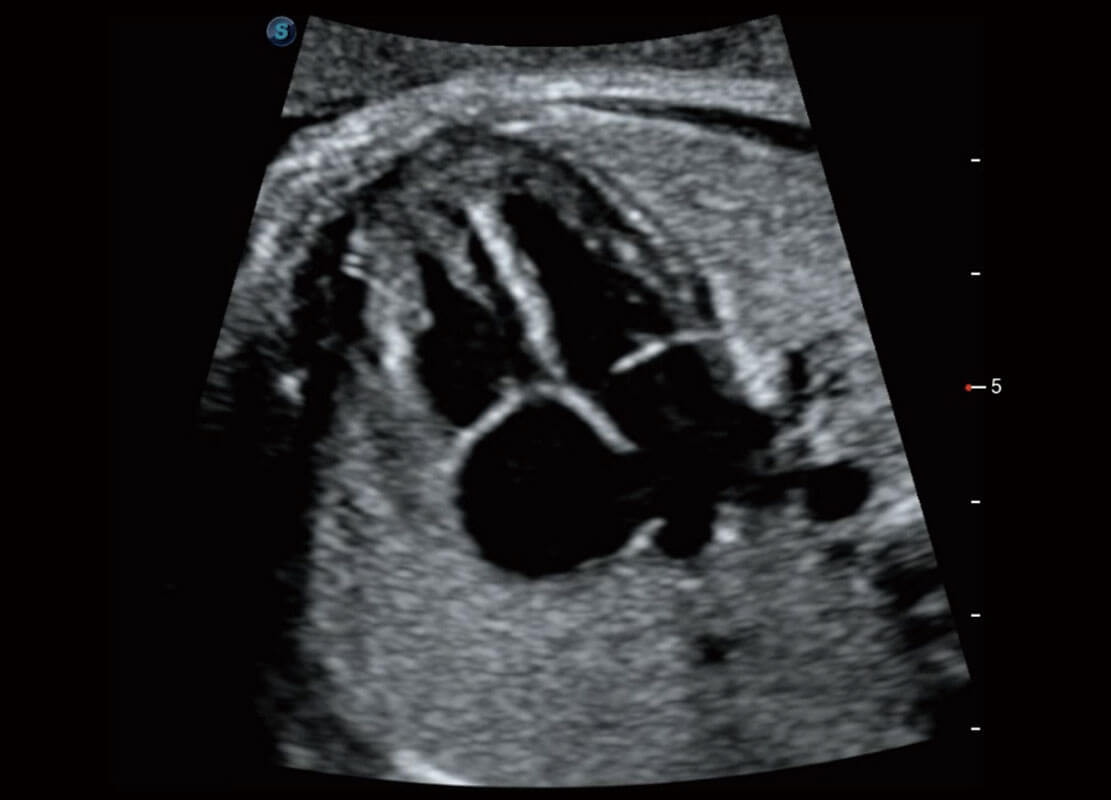

P60在胎儿早孕期超声筛查中为您带来优异的图像质量。

早孕-胎心

高分辨率容积成像-早孕胎儿

光影成像-孕囊